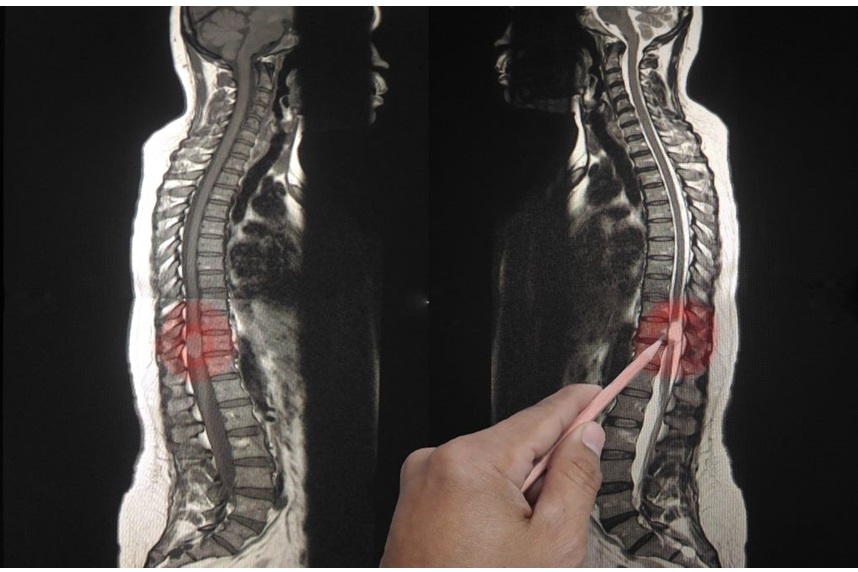

The diagnosis of syringomyelia is based on a combination of factors. One of these is the evaluation of the patient's symptoms and medical history. If, following anamnesis and physical examination, syringomyelia is suspected, imaging tests will be performed to confirm the diagnosis. MRI is the most common imaging method used to diagnose syringomyelia. With this investigation, doctors can determine if there is a syrinx in the spinal cord or any other anomaly, such as a tumor. CT scans and other investigations may also be used.[2][3]